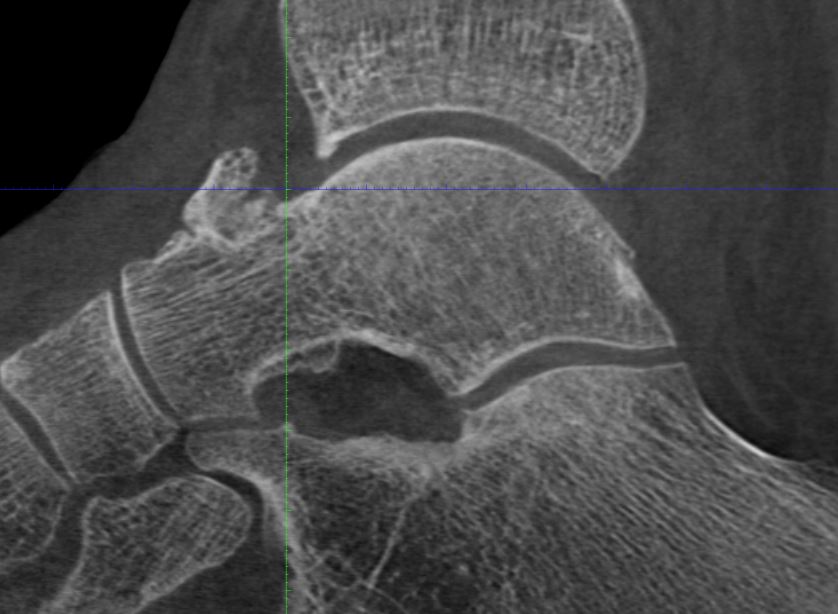

schweres knöchernes Impingement des OSG